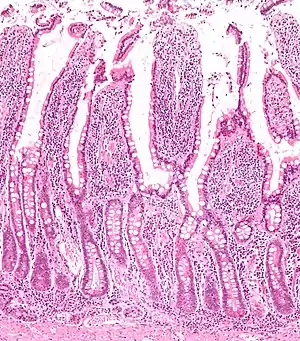

Microanatomy

The three sections of the small intestine look similar to each other at a microscopic level, but there are some important differences. The parts of the intestine are as follows:

| Layer | Duodenum | Jejunum | Ileum |

| Serosa | 1st part serosa, 2nd–4th adventitia | Normal | Normal |

| Muscularis externa | Longitudinal and circular layers, with Auerbach's (myenteric) plexus in between | Same as duodenum | Same as duodenum |

| Submucosa | Brunner's glands and Meissner's (submucosal) plexus | No BG | No BG |

| Mucosa: muscularis mucosae | Normal | Normal | Normal |

| Mucosa: lamina propria | No PP | No PP | Peyer's patches |

| Mucosa: intestinal epithelium | Simple columnar. Contains goblet cells, Paneth cells | Similar to duodenum, but the intestinal villus is long | Similar to duodenum, but the intestinal villus is short |

Digested food is now able to pass into the blood vessels in the wall of the intestine through either diffusion or active transport. The small intestine is the site where most of the nutrients from ingested food are absorbed. The inner wall, or mucosa, of the small intestine, is lined with simple columnar epithelial tissue. Structurally, the mucosa is covered in wrinkles or flaps called circular folds, which are considered permanent features in the mucosa. They are distinct from rugae which are considered non-permanent or temporary allowing for distention and contraction. From the circular folds project microscopic finger-like pieces of tissue called villi (Latin for "shaggy hair"). The individual epithelial cells also have finger-like projections known as microvilli. The functions of the circular folds, the villi, and the microvilli are to increase the amount of surface area available for the absorption of nutrients, and to limit the loss of said nutrients to intestinal fauna.

Each villus has a network of capillaries and fine lymphatic vessels called lacteals close to its surface. The epithelial cells of the villi transport nutrients from the lumen of the intestine into these capillaries (amino acids and carbohydrates) and lacteals (lipids). The absorbed substances are transported via the blood vessels to different organs of the body where they are used to build complex substances such as the proteins required by our body. The material that remains undigested and unabsorbed passes into the large intestine.